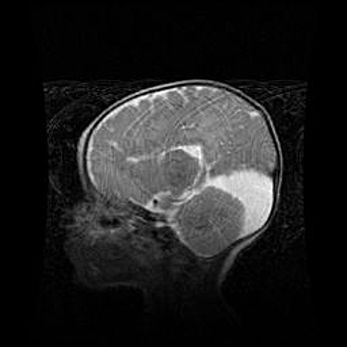

Мальформация Денди-Уокера. Киста задней черепной ямки.

Агенезия мозолистого тела.

Возраст: 2,5 месяца

Вес: 2420 г

Пол: женский

Окружность головы: 37 см

Срок гестации: 32 недели

Мальформация Денди—Уокера — редкий вид патологии ЦНС, представляющий собой врожденный порок развития каудального отдела ствола и червя мозжечка, ведущий к неполному раскрытию срединной (Мажанди) и латеральных (Лушка) апертур IV желудочка мозга. Для этогно синдрома характерна триада симптомов: гипотрофия червя мозжечка и/или полушарий мозжечка, кисты задней черепной ямки, гидроцефалия различной степени. В 70% случаев порок сочетается и с другими аномалиями головного мозга, в частности с агенезией мозолистого тела.